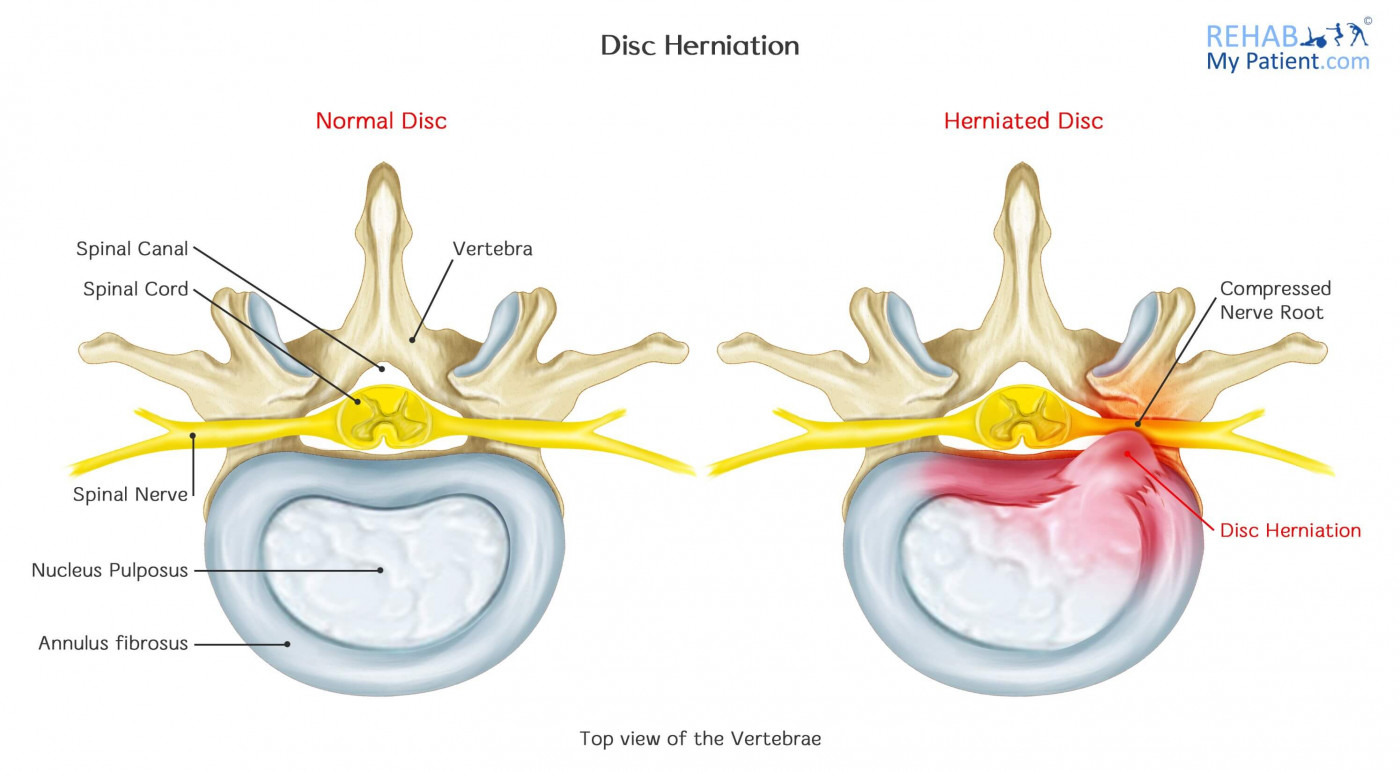

КТ-протрузии дисков: Визуализация и классификация